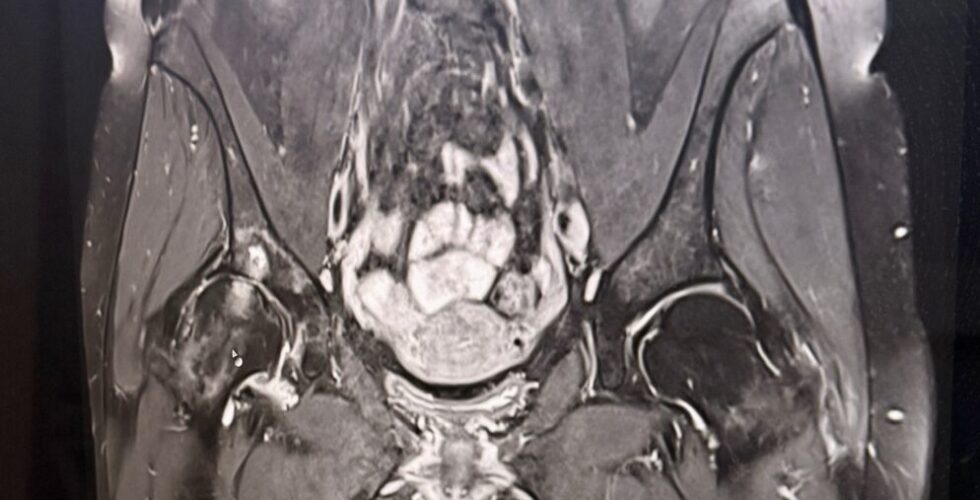

Coxarthrose im fortgeschrittenen Stadium

Seit Oktober 2024 begleitet mich meine Coxarthrose (rechte Hüfte). Schweregrad bei Diagnose: 3,5 von 4. Ich konnte keinen Schritt mehr gehen. Es war hoch akut. „Da landen Sie sicher in nächster Zeit unter dem Messer“, so der diagnostizierende Arzt. Ich verlor allerdings mein Lächeln nicht auf den Lippen und reagierte